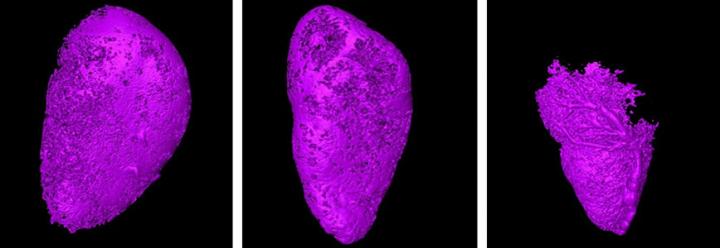

The team tested their new method on mice with breast cancer cells inserted into their lymph nodes. They injected a contrast agent at a slow, steady pace into the lymph nodes upstream of those carrying the cancer cells. As the contrast agent made its way through the lymphatic system, the researchers were able to map out its movement using micro-CT.

Initially, the researchers did not observe any change in the flow of the contrast agent. However, after 28 days of injecting the cancer cells into the lymph nodes, they had divided and grown to a point where they blocked the flow of the contrast agent, creating empty pockets in the scan that did not have any contrast agent.

By comparing the shape of the lymph node and the areas that contained the contrast agent, the researchers were able to get a clear picture of the presence of cancer cells there.